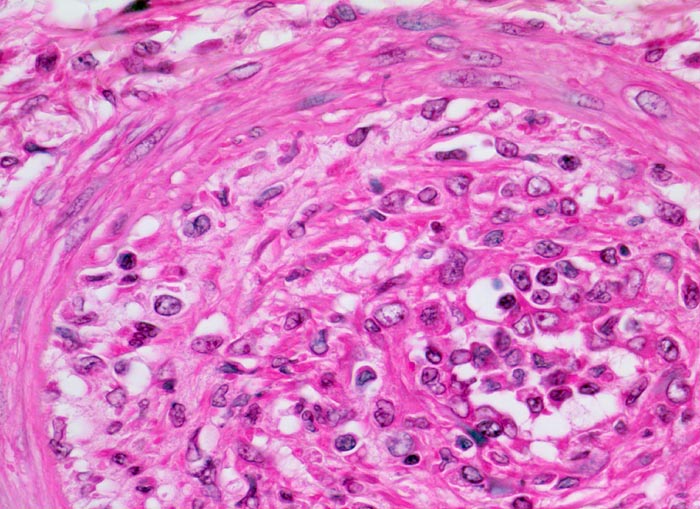

akute Transplantatverwerfung: intimale Arteriitis

Kleine Arterie mit akuter Transplantatvaskulopathie mit Ödem und Infiltration der Intima durch Histiozyten und Lymphozyten, Immunoblasten und Myofibroblasten. Zwischen den zellulären Infiltraten neugebildete kollagenöse Matrix. Das Lumen ist stark eingeengt. Die Media hingegen weist keine entzündlichen Veränderungen auf. Die geschwollenen aktivierten Endothelzellen sind arkadenförmig von der Basalmembran abgelöst. Unter den abgelösten Endothelien finden sich Infiltrate von Entzündungszellen (=Endothelialitis).

Der Befund entspricht einer intimalen Arteriitis. Wenn wie im vorliegenden Fall mehr als 2/3 des Gefässquerschnittes obliteriert ist, kommt es zur funktionellen Einschränkung. Die vorliegende entzündlich bedingte Intimafibrose lässt sich von degenerativ bedingten Intimaveränderungen (Hypertonie, Diabetes...) aufgrund der fehlenden Elastose bei vaskulärer Abstossung unterscheiden (nur sichtbar mit Spezialfärbung z.B. EvG).